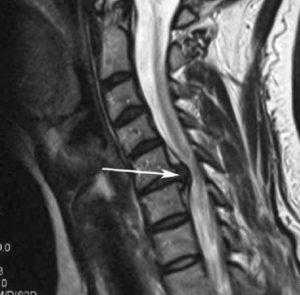

Стеноз шейного отдела вследствие грыжевого выпячивания.

С лечением компрессии шейного отдела позвоночника, пояснично-крестцового или грудного, медлить нельзя! Долгое компрессионное воздействие может вызвать гибель жизненно важных структур, в итоге привести к параличу рук или ног, тяжелым необратимым мозговым нарушениям, критической несостоятельности мочеполовой системы, сердца, дыхательного центра. Профессионально оценить всю серьезность клинического случая, грамотно рекомендовать тот или иной вид терапии, может - невролог, нейрохирург, ортопед.